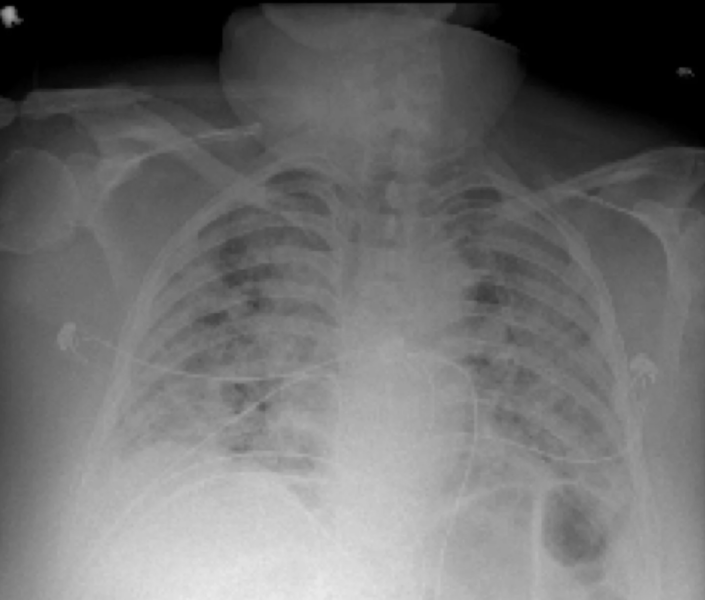

This photo gallery shows the variety of radiological presentations of COVID-19 (SARS-CoV-2) in medical imaging, including computed tomography (CT), radiograph X-rays, ultrasound, echocardiograms and magnetic resonance imaging (MRI). The radiology images show examples of typical COVID pneumonia in the lungs and the numerous complications the virus causes in the body in multiple organs, including the brain, kidneys, heart, abdomen and vascular system.

Ultrasound, especially hand-held ultrasound imaging devices, have become a primary imaging modality for novel coronavirus because of the ease to bag the device and sterilize it after use. CT and mobile X-ray systems are also used as front-line imaging systems for COVID-positive or suspected COVID patients.